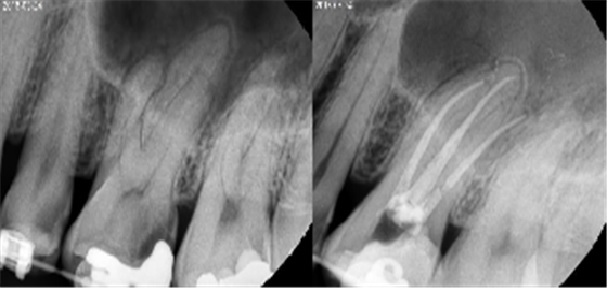

치료전후사진